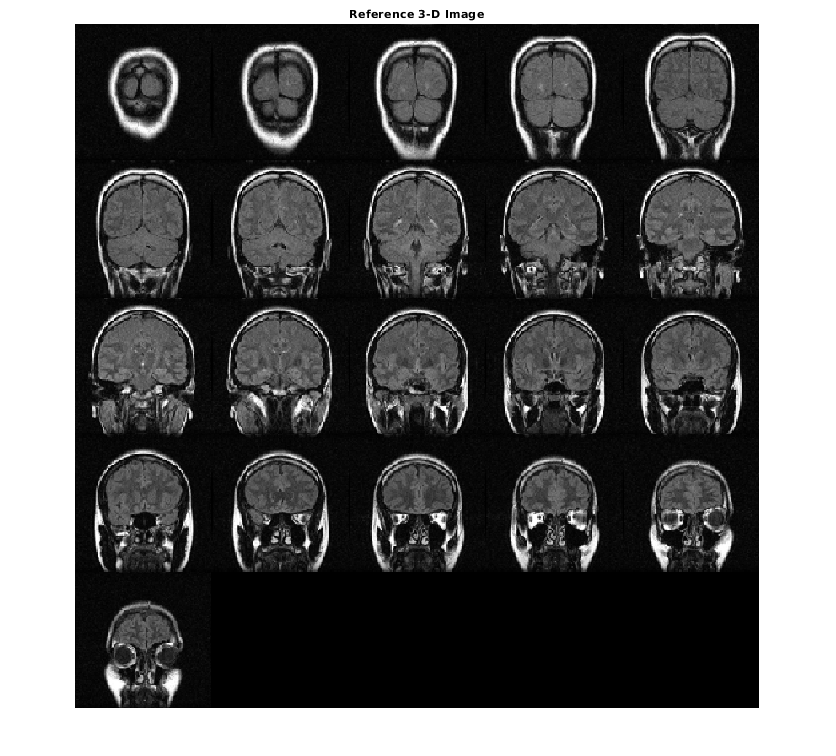

Отобразите ссылочный объем как срезы. Чтобы отобразиться правильно на экране, ссылочный объем уменьшается на коэффициент 0,5 использований imresize.

ref_downsized = imresize(ref,0.5);

figure

montage(ref_downsized,'DisplayRange',[])

title('Reference 3-D Image')

Figure contains an axes object. The axes object with title Reference 3-D Image contains an object of type image.